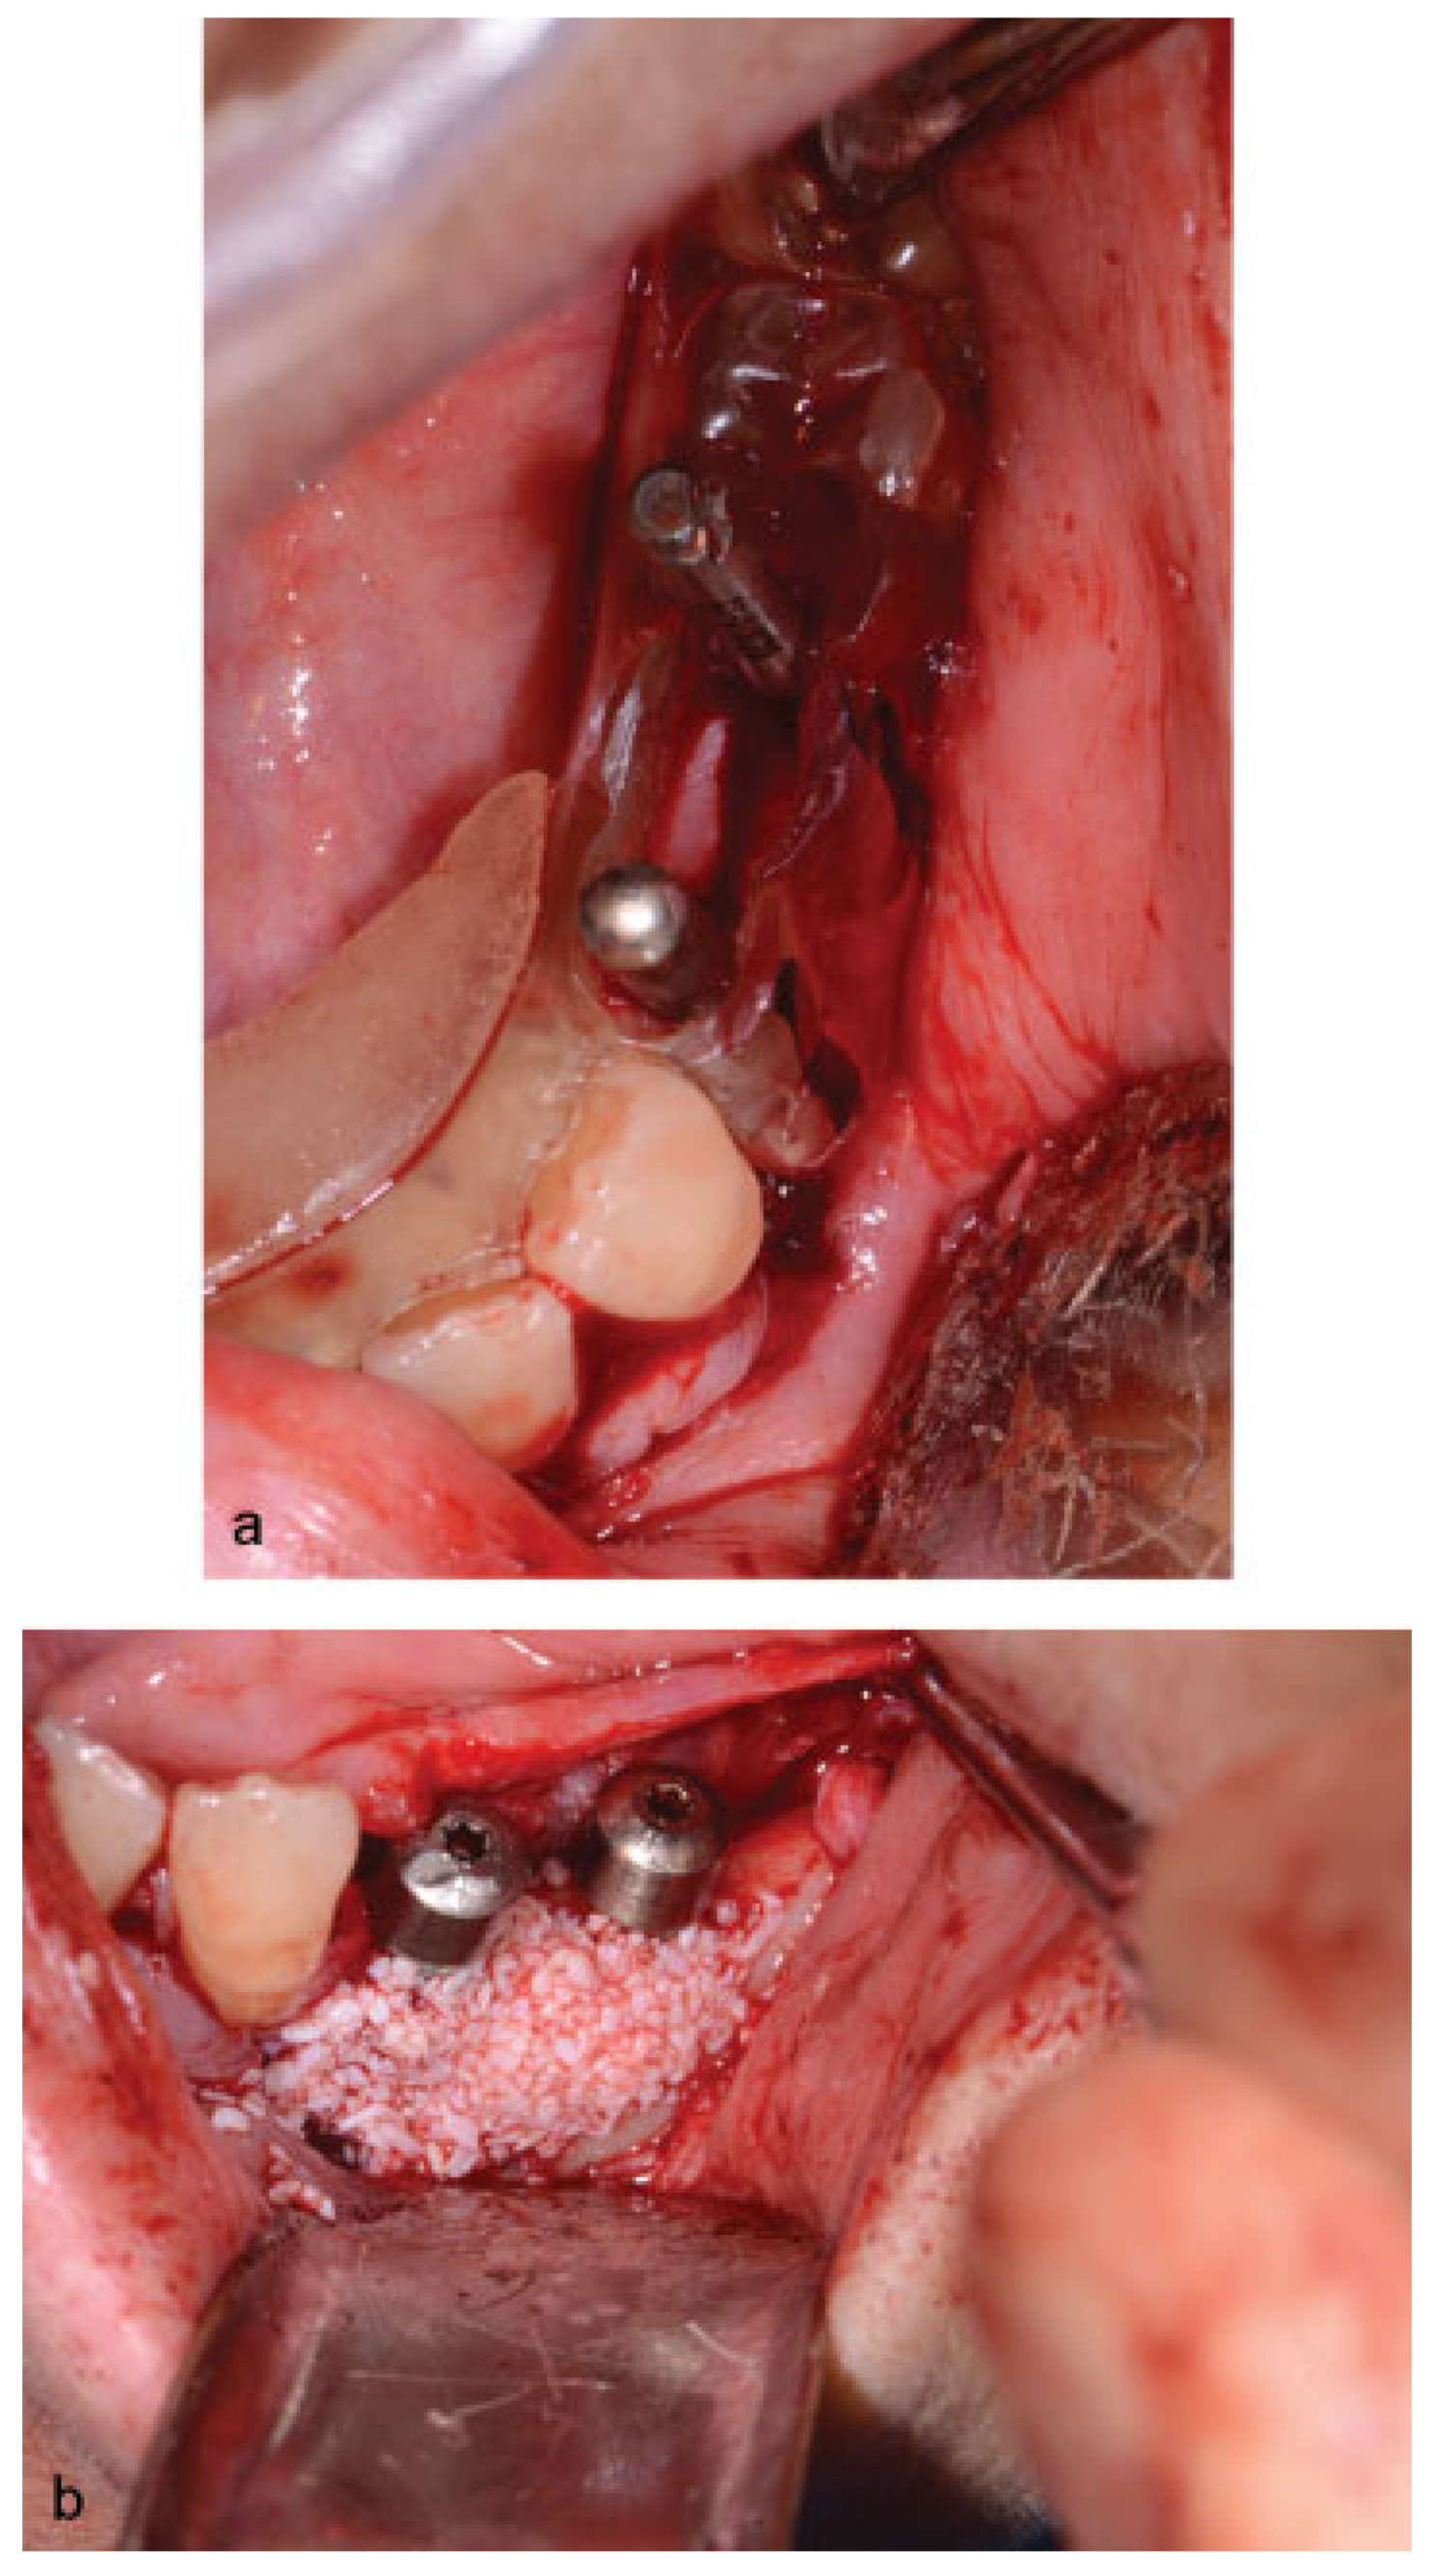

Figure 5. (a) Transoperative view of the iliac crest bone graft. (b) Transoperative view of corticocancellous bone graft blocks placed. (c) Transoperative view of cancellous bone covering the block grafts.

Figure 7. (a) Intraoral view demonstrating the parallelism between the inferior implants placed. (b) Intraoral view demonstrating the alloplastic bone graft covering the exposed threads of the implants.

A 46-year-old Caucasian female presented to the Oral Surgery Department at Alameda County Medical Center–Highland General Hospital, complaining of dental pain in maxillary left region for 2 months. Her medical history was significant for hypertension and congestive heart insufficiency for which she takes enalapril, carvedilol, furosemide, and Klor-Con (Klor- Con®, Upsher-Smith Laboratories, Inc., Morristown, NJ) (potassium chloride). She is allergic to codeine. She has a 10 pack- year history of smoking and a remote history of methamphetamine use. Her past surgical history is significant for parathyroid carcinoma, which resulted in primary HTP. She reported that time weight loss, hives, insomnia, fatigue, and bone pain before surgical excision performed 17 years ago. No uterine or kidney lesions were present. She also reported that her brother had a jaw tumor, not surgically treated, because the “jaw growth stopped.” Unfortunately, her brother does not live in the city, and a better investigation concerning his disease could not be performed. Extraoral examination revealed a small swelling in the left mandibular border. Intraorally, the patient presented with poor hygiene with multiple extensive dental caries and periodontal disease. An asymptomatic and firm posterior left mandibular swelling was also present, with buccal and lingual expansion. Radiographic and computed tomography (CT) scan examination revealed a 5-cm mixed radiolucent and radiopaque image in the left mandibular body with well-defined borders and base expansion (Figure 1 and Figure 2a,b). An incisional biopsy was obtained with an intraoral approach which was diagnosed as a benign fibro-osseous lesion, consistent with ossifying fibroma. Initial laboratory analysis prior surgery showed a small increase in serum calcium of 10.5 mg/dL (8.4–10.2 mg/dL). Based on these findings and with the history of parathyroid carcinoma, the patient was referred to an endocrinologist. CT scan of the neck was unequivocal for recurrence and no correction of serum calcium was necessary. The association of ossifying fibroma with primary HPT due parathyroid carcinoma, with a family history of a similar jaw lesion, led to a high suspicion of HPT-JT syndrome. It was extensively discussed with the patient, but she refused to perform any genetic test. Our treatment planning initially included the extraction of the left inferior premolars, which had extensive caries lesions and mobility, performed before the lesion surgical removal. It would enable a better wound closure after resection. Three months later (2010 March), the ossifying fibroma was surgically resected with 5 mm margins (Figure 3) using an intraoral approach, and a 2.4-mm reconstruction plate was placed from the left mandibular ramus to the parasymphysis (Figure 4a–c). The postoperative course was remarkable only for neurosensory disturbance in the left inferior alveolar nerve, which improved but was not completely resolved after 3 years of follow-up. Seven months later (2010 October), using an extraoral approach, the patient underwent a left mandibular reconstruction using her left posterior iliac crest, as well as the right anterior iliac crest. The corticocancellous blocks were secured with 2.4 mm monocortical screws, while cancellous bone chips were inserted between the block grafts (Figure 5a–c). Although regular follow-ups were performed within the first 4 postoperative months, the patient recently returned to the oral surgery clinic for revaluation in 2012. Clinical and radiological examinations (Figure 6) were performed, and oral rehabilitation with dental implants was planned (June 2012). The patient subsequently underwent a third surgical intervention, under local anesthetic and intravenous sedation. The remaining maxillary teeth were extracted, followed by osteoplasty and placement of four implants: two anterior axially placed and two posterior tilted placed. At the same operating time, monocortical screws were from the mandible and three implants were placed in the region of teeth 20, 21, and 28, and alloplastic bone graft was placed covering the exposed threads of the implants (Figure 7a,b). A temporary superior and inferior prostheses were subsequently placed, and a period of 6 months for implant osseointegration before final prosthesis rehabilitation is being observed. The patient is currently followed regularly and, after 3 years of surgical resection, no evidenceof tumor recurrence is seen (Figure 8). Therefore, no evidence of parathyroid carcinoma recurrence is seen after 21 years of endocrinological follow-up.